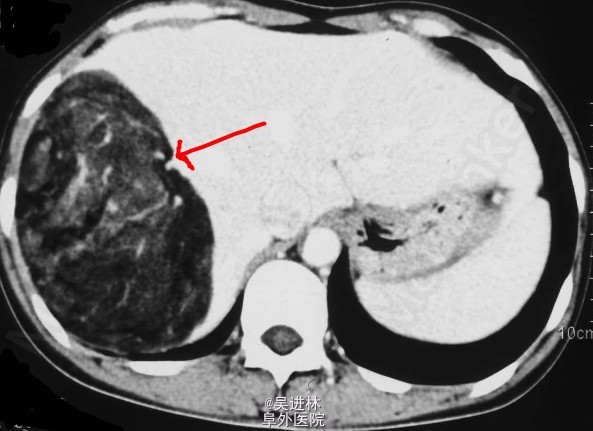

肝巨大脂肪瘤

患者男,56岁,体检B超发现肝区巨大占位就诊。手术病理提示肝脏脂肪瘤。本病罕见。